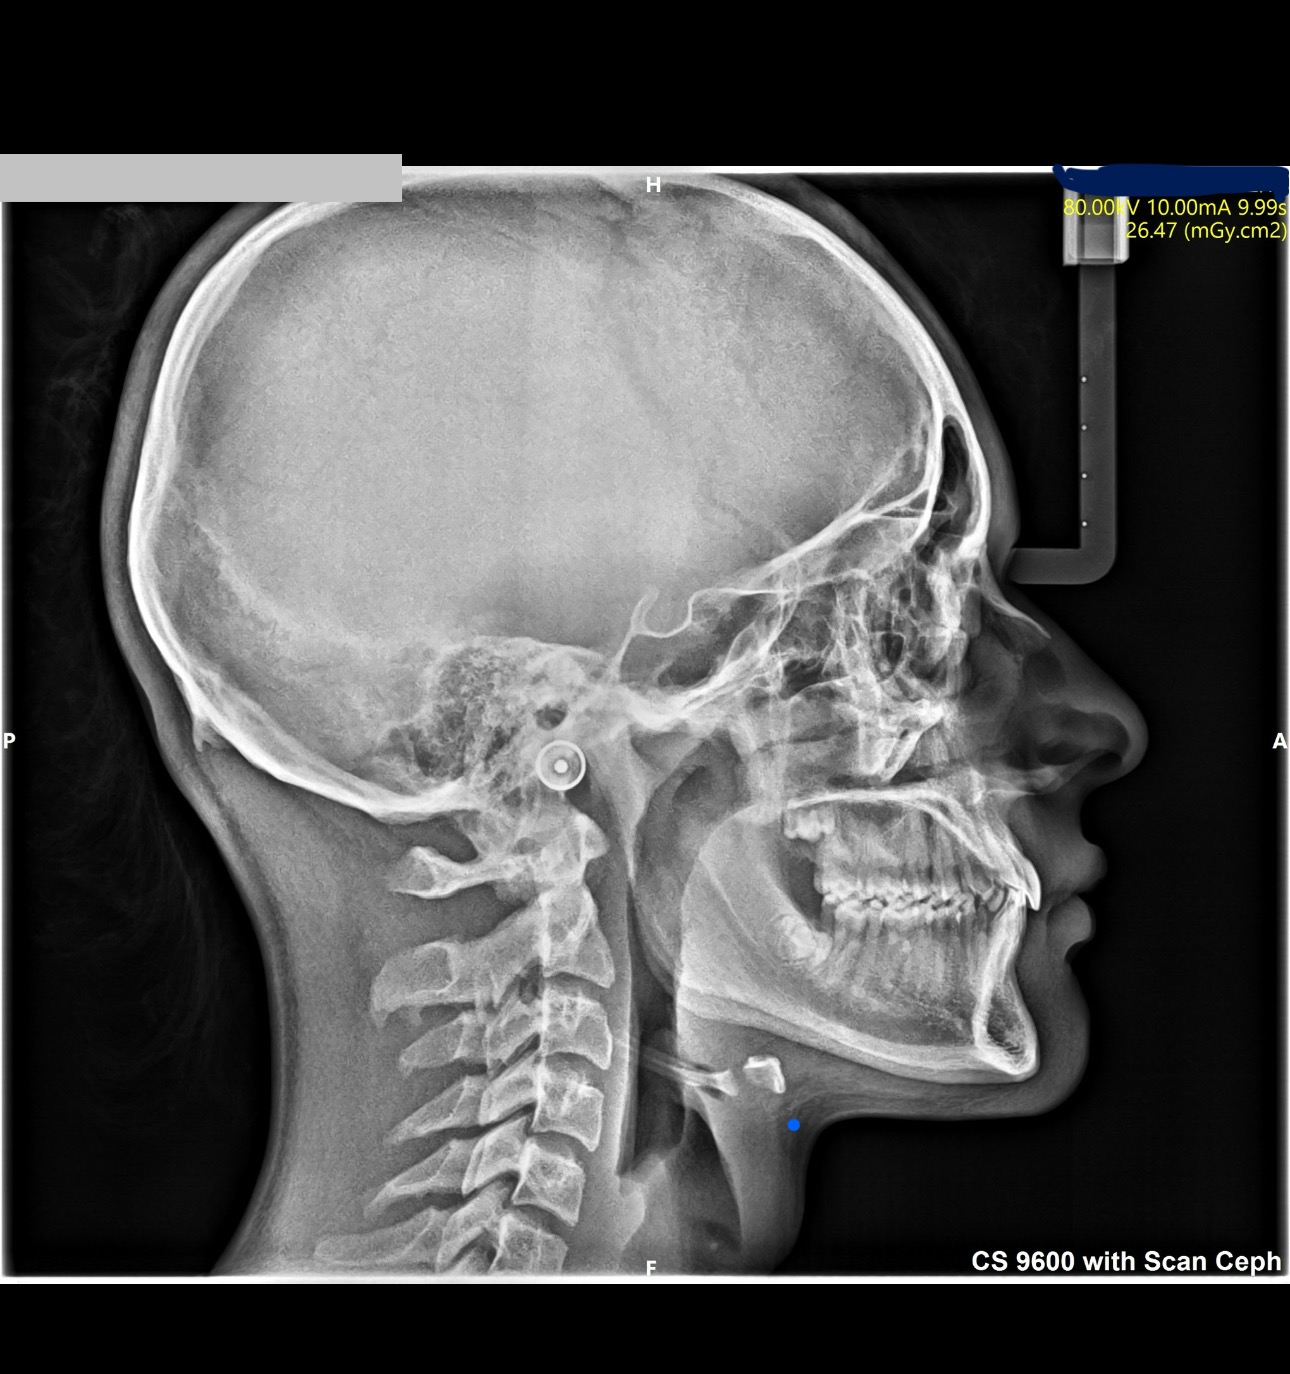

just made a few scans and im considering palete expander of face mask, ideally both?

Rapid Palatal Expander (RPE) + generic face mask